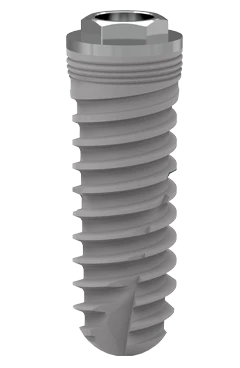

Conexión hexagonal externa universal

Ápice activo

Tratamiento de superficie con Titansure